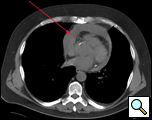

| Figure 1. CT scan showing pericardial effusion. |

Hemodynamically stable patients with an undiagnosed pericardial effusion are well suited for a thoracoscopic window. When pericardial, pleural, or pulmonary pathology co-exist and require diagnosis or therapy, a thoracoscopic approach is ideal. If a large piece of pericardial tissue is needed for culture or pathological examination, thoracoscopy provides good exposure and allows for an adequate specimen to be sampled [1]. Known benign effusions that re-accumulate after aspiration should be treated with a thoracoscopic window. Drainage of a purulent pericardial effusion, and early fungal or tuberculous pericarditis where resection of the pericardium to prevent future pericardial constriction is required, are also indications. In patients with descending mediastinitis a window or resection of the pericardium may be warranted as part of the mediastinal debridement. Loculated effusions situated unilaterally or posteriorly are more easily approached thoracoscopically (Figure 1).

A CT scan provides information as to the location and size of the effusion, whether there are loculations, the nature of the parietal pericardium, and associated pulmonary or pleural pathology. Echocardiography provides a dynamic assessment of the physiologic impact of the effusion on myocardial function which helps determine if the patient will be hemodynamically stable to undergo a thoracoscopic pericardial window (Echo 1).